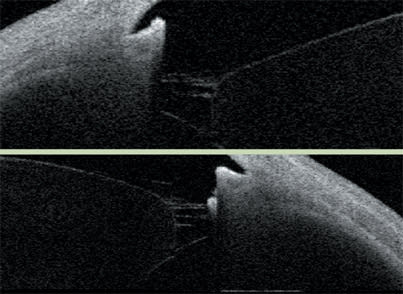

Imaging illustrates a very narrow angle and the need for a lensectomy. The lensectomy accomplished the goal of a much more open anatomy.